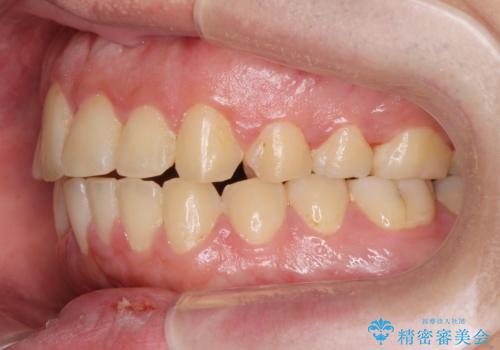

見た目、噛み合わせが大きく改善し、大変喜んでいただくことができました。

正中過剰埋伏歯で生じた前歯の審美障害 矯正治療での改善

- 20代男性